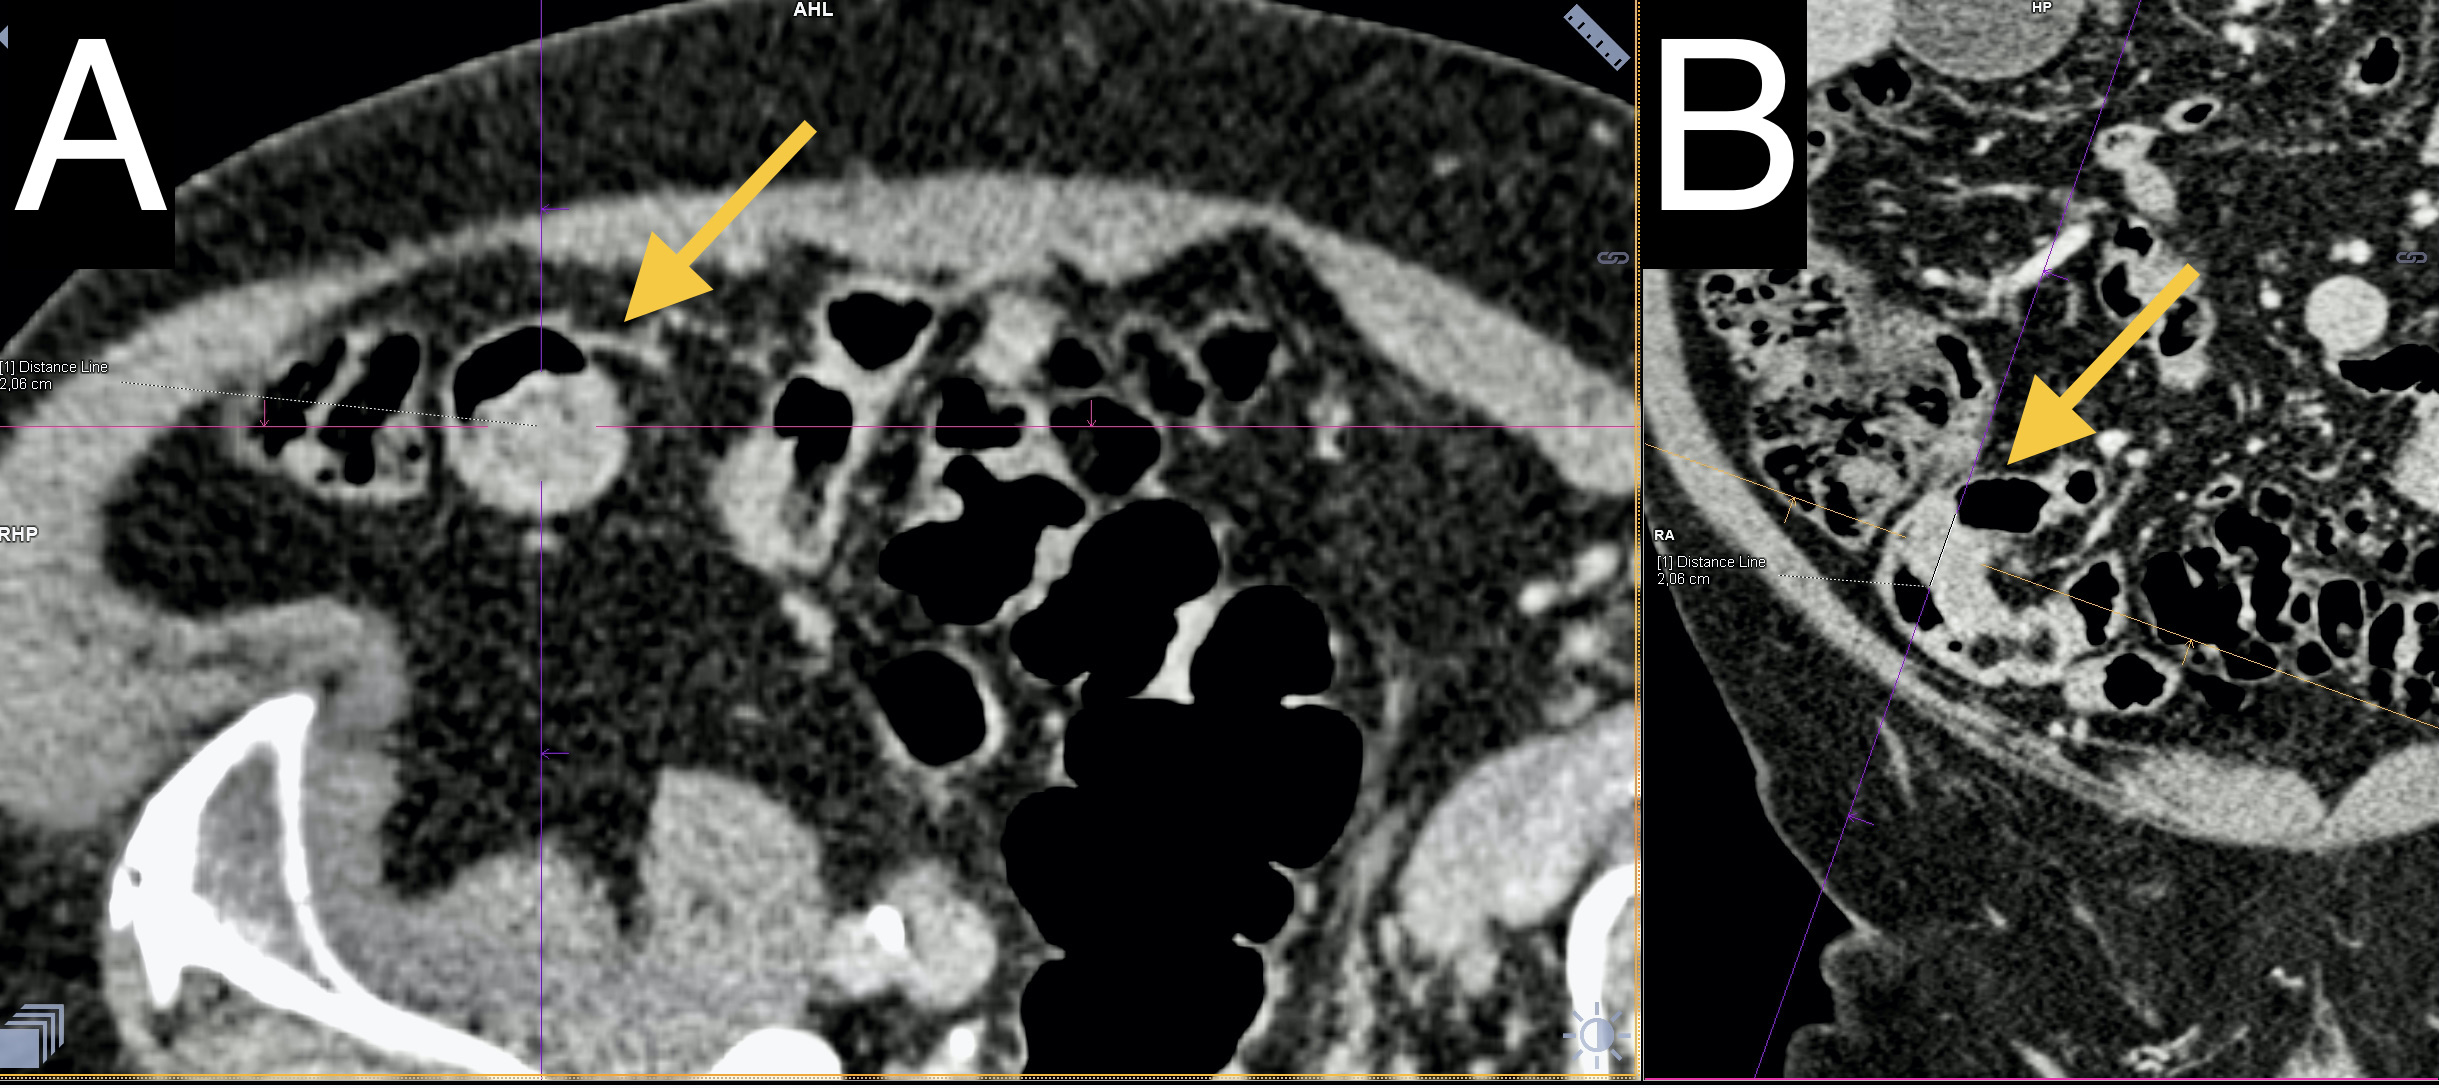

Intussusception of the small intestine occurs when one part of the intestine telescopes into another, causing ischemia and obstruction. This condition is rare in adults, with the most common cause being a benign tumor in the intestinal wall. This paper presents a case of ileal intussusception caused by a submucosal lipoma in the form of a polyp. The intussusception resulted in mild discomfort, and the diagnosis was established through ultrasound and computed tomography scans. Surgical treatment was performed, involving laparoscopic reduction of the intussusception, segmental resection of the intestine, and end-to-end anastomosis. The postoperative course was uneventful.